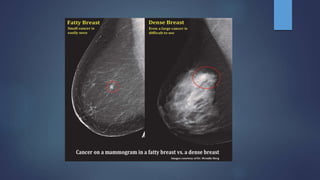

 A 'Mass' is a space occupying 3D lesion seen in two different

projections.

 If a potential mass is seen in only a single projection it should be

called a 'asymmetry' until its three-dimensionality is confirmed.